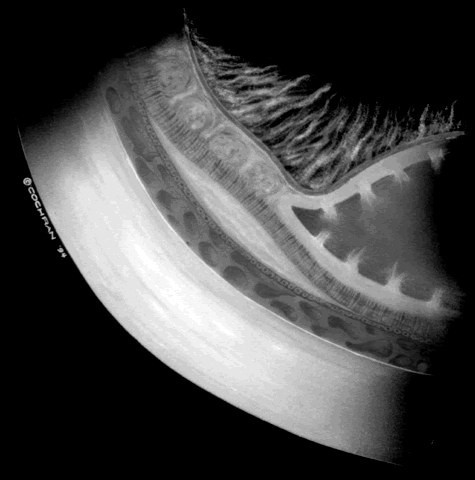

When first assessing a child's retinal detachment, one must judge the amount of effusive versus tractional detachment (Figs. 4 and 5). Scleral buckling would be considered for the child who shows a predominately effusive stage 4B detachment as opposed to a stage 4 predominately tractional detachment, for which lens-sparing vitrectomy may be recommended.24 For a child who has a great deal of retrolenticular touch, lensectomy/ vitrectomy and membrane peeling would be recommended. It appears that the “window” for lens-sparing vitrectomy may be rather brief. In one series, the postconceptual age of the lens-sparing vitrectomized eyes was 42.6 weeks, as opposed to 46.9 weeks for eyes that needed lensectomy/vitrectomy and membrane peeling. This small time difference in the postconceptual age shows the often rapid evolution of this detachment from one in which the lens is salvageable to one in which the lens is unsalvageable. This highlights the need for timely screening of eyes, identification of eyes with progressive disease, and rapid intervention.25

Fig. 4. A predominantly effusive stage 4B retinal detachment.

Fig. 5. A predominantly tractional stage 4B retinal detachment.